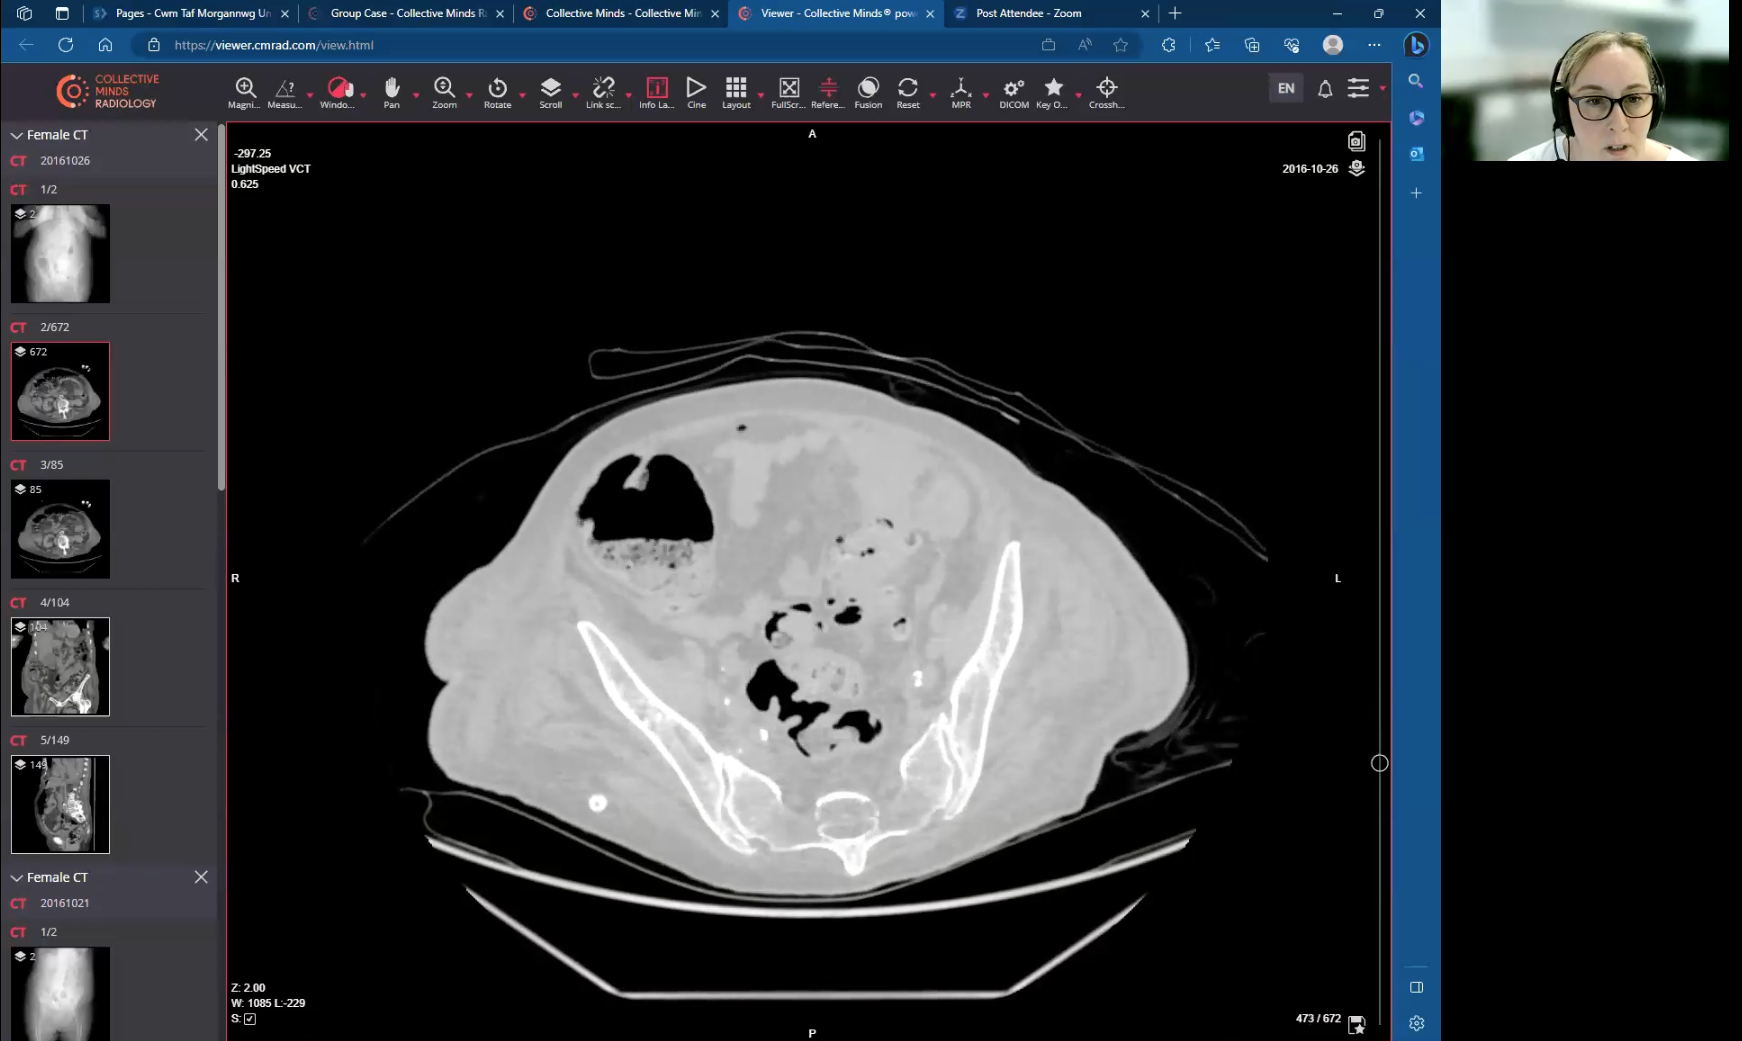

CT Colonography Course (On demand)

01. CT Colon Introduction.

06. Image Review and Interpretation.

08. CT Colon Pathology.